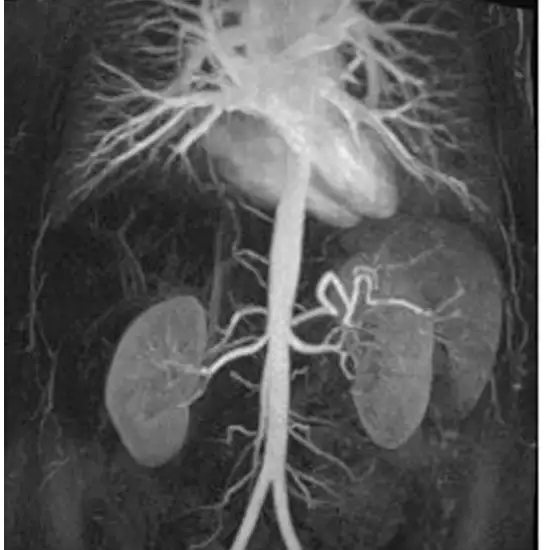

An abdominal angiography examines your abdominal blood vessels (abdomen). It may be used to evaluate blood flow to abdominal organs, such as the liver and spleen.

Abdominal angiograms diagnose vascular problems such as ballooning of a blood vessel (aneurysms), blockages, and narrowing of a blood vessel (stenosis).

MRA (Magnetic Resonance Angiography) screening of the Angiography Abdomen is a non-invasive radiology test used to evaluate the condition of the blood vessels of the abdomen and surrounding tissue. MR Angiography Abdomen is done to look for the abdominal abnormalities and the surrounding area.